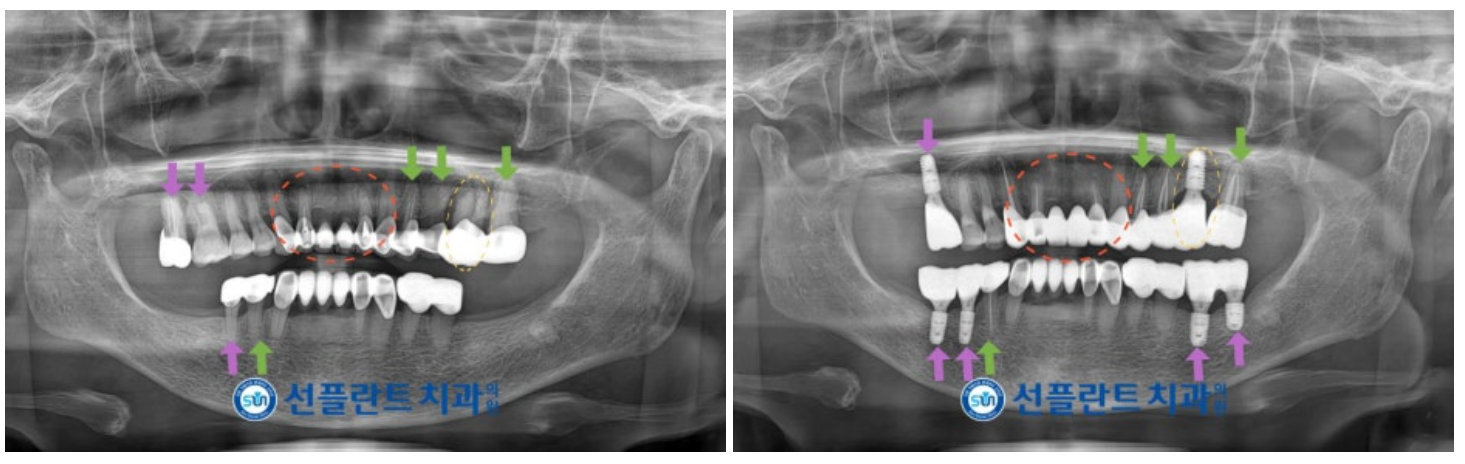

잇몸치료를 진행하면서

통증을 호소하셨던

위턱 왼쪽 첫 번째 큰 어금니(#26)를

발치 후 주변 염증 조직을 깨끗하게 제거하고

소독하는 과정을 거쳤으며,

골소실이 심한 상태로

바로 임플란트 식립을 진행하지 않고

지연 식립을 결정하였으며

기다리는 동안 다른 부위의 치료를

도와드리기로 하였습니다.

잇몸 퇴축과 우식이 동반된

기존 앞니 보철물을

내부의 치아에 손상이 생기지 않도록

조심스럽게 제거한 뒤

신경치료가 필요한 치아는

신경치료를 진행해 드렸으며

최종 보철물은

자연치아와 강도가 유사하고

심미적인 지르코니아로

마무리해 드렸습니다.

보철물 교체가 필요한

다른 치아들 역시 신경치료 후

크라운 수복을 진행해 드렸으며

앞니와 같은 지르코니아 보철물로

도와드렸습니다.